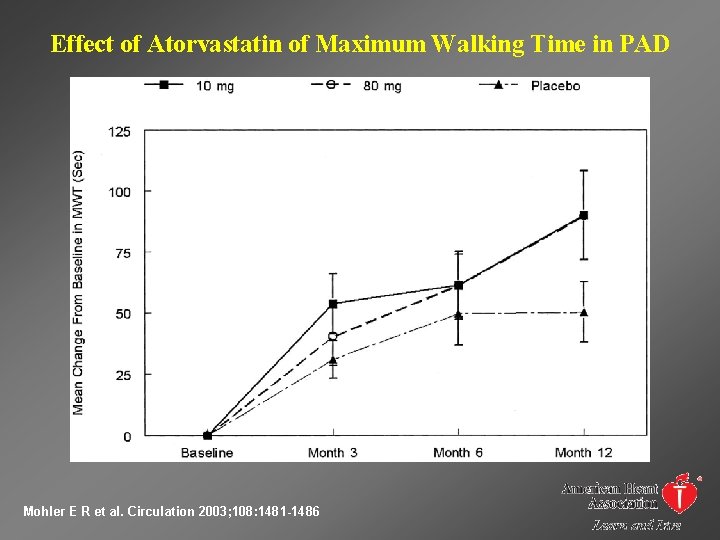

Effect of Atorvastatin of Maximum Walking Time in PAD Mohler E R et al. Circulation 2003; 108: 1481 -1486